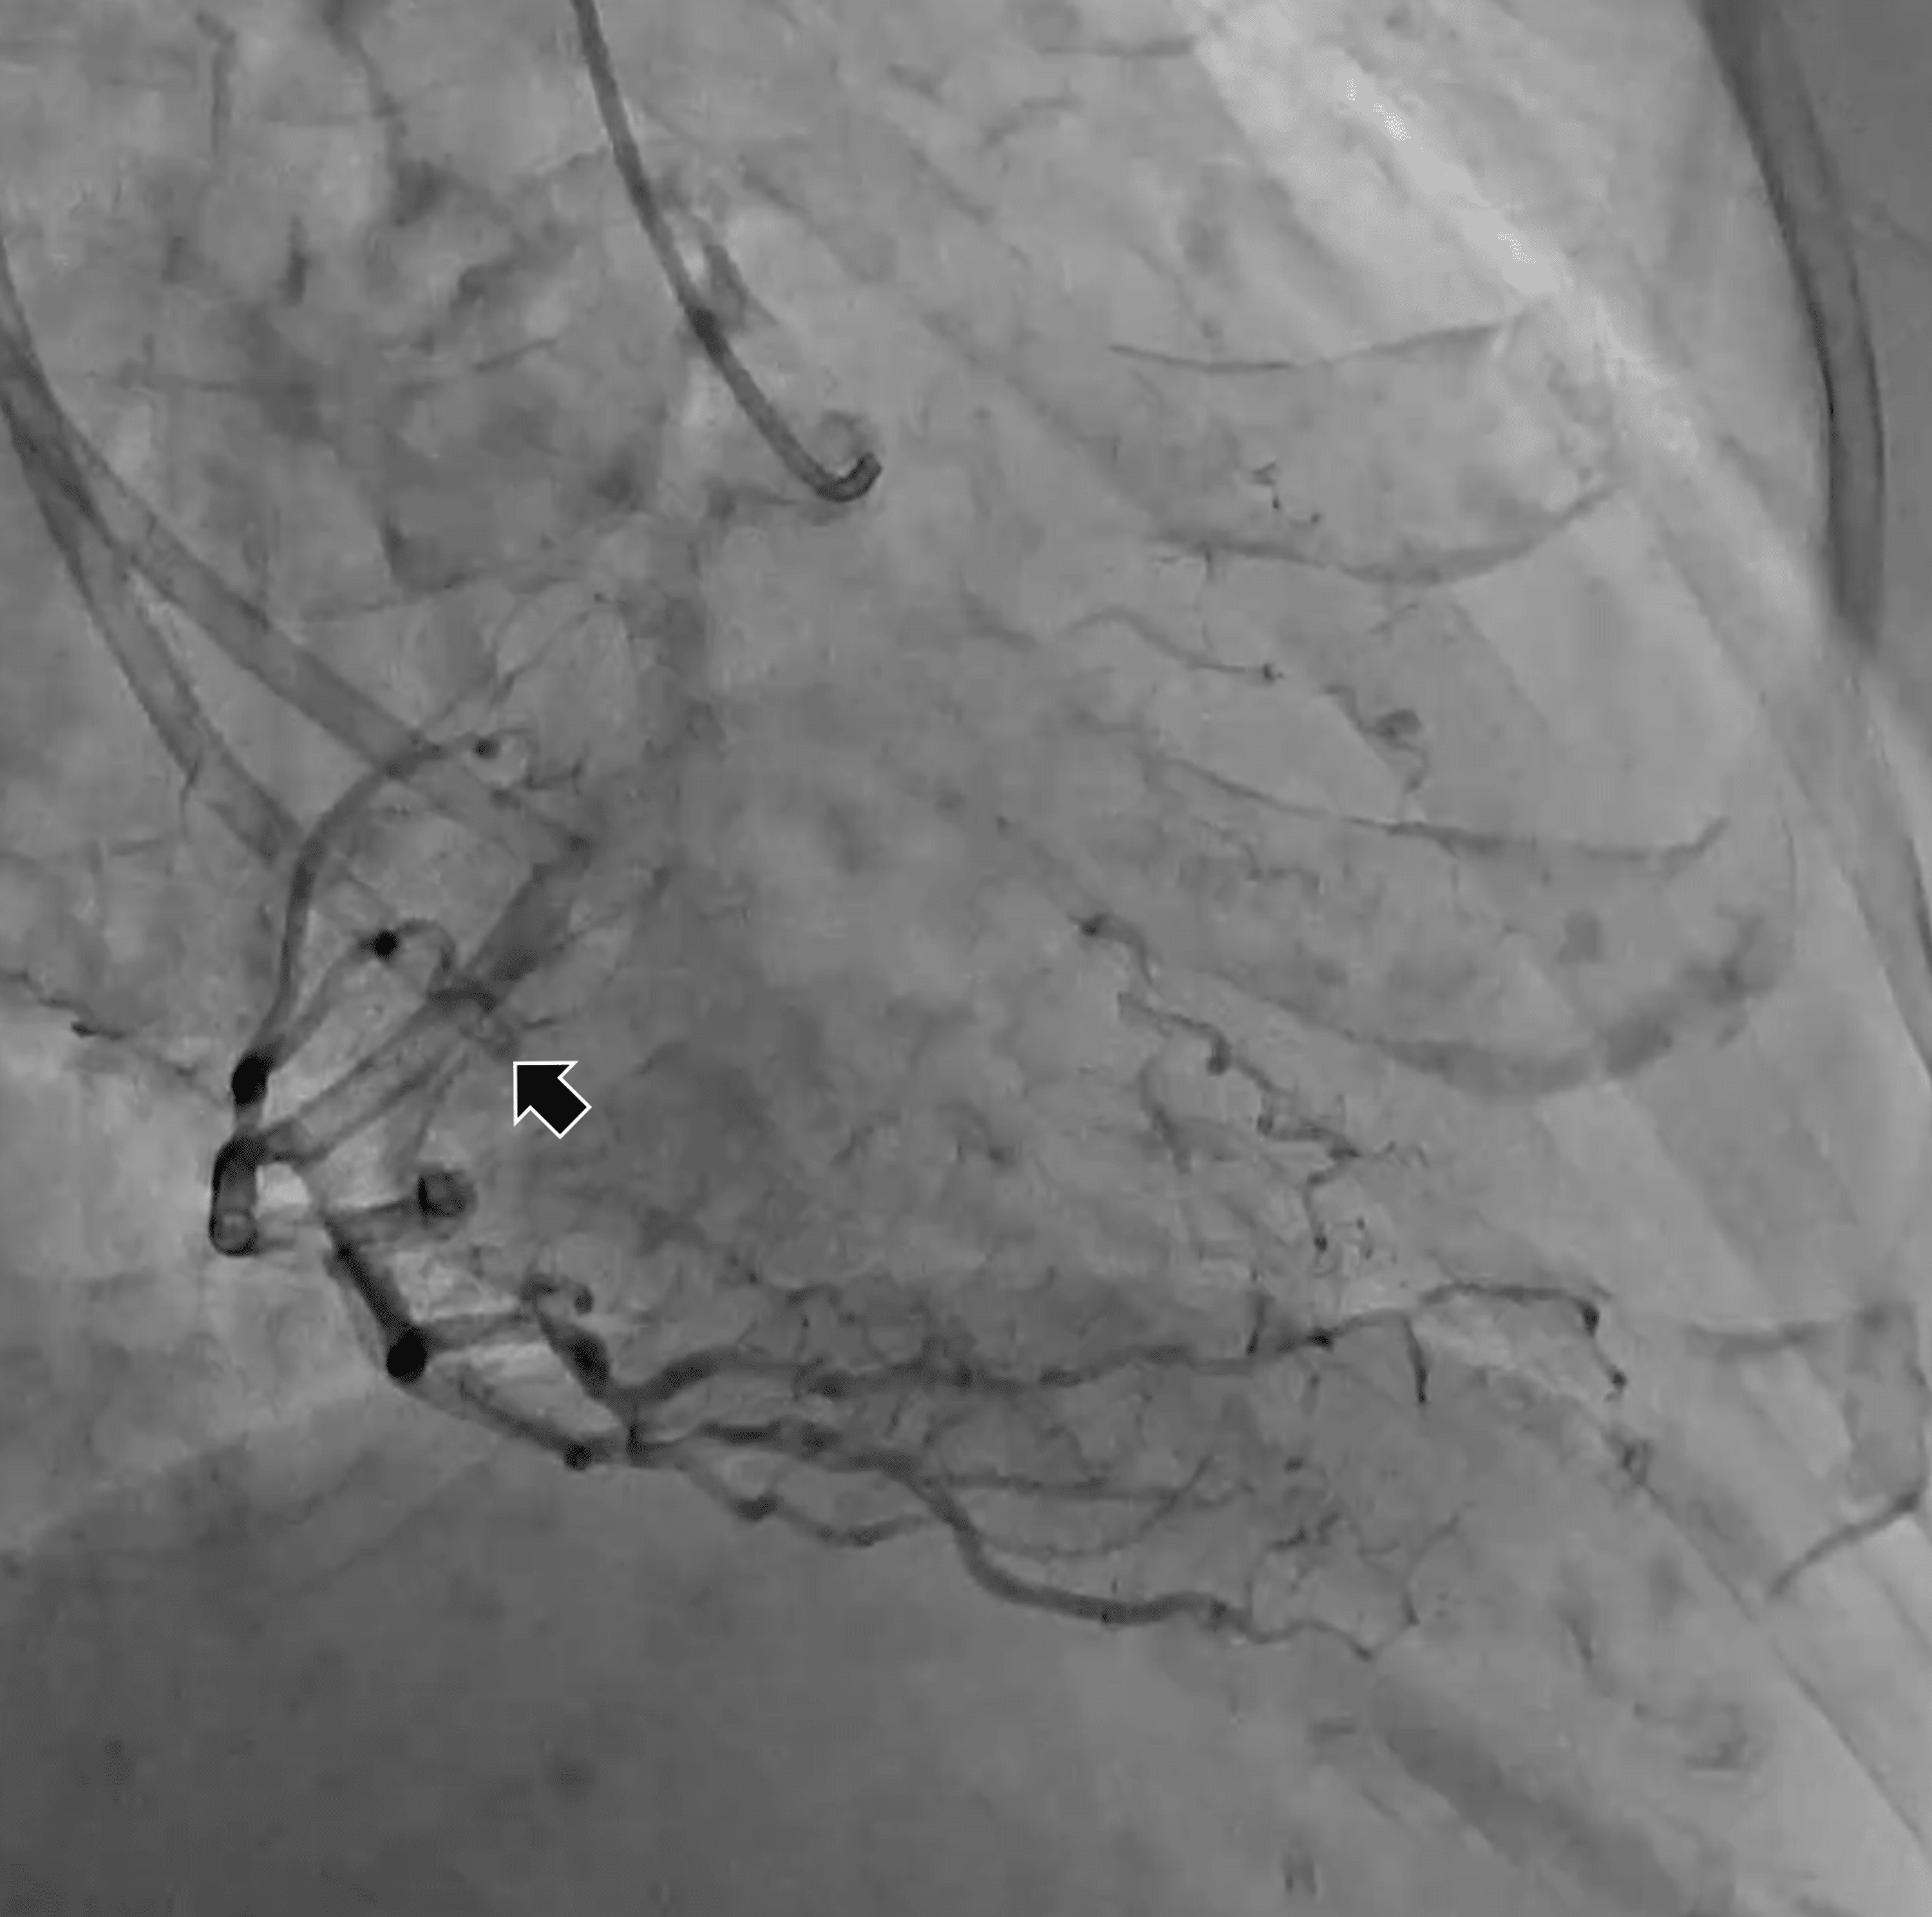

Cureus Endovascular Retrieval of a Fractured Tunneled Hemodialysis Catheter Fracture Central Venous Gibson, in clinical radiology, 2006. complications of port systems are divided into early (≤ 30 days after. the number and severity of complications increase with catheter size, multiple catheter implantations, and a. a central line venous catheter fracture is another dysfunction seen most. central venous catheter (cvc) is a cannula placed in a central vein (e.g.. Catheter Fracture Central Venous.

Cureus Endovascular Retrieval of a Fractured Tunneled Hemodialysis Catheter Fracture Central Venous central venous catheter (cvc) is a cannula placed in a central vein (e.g. the number and severity of complications increase with catheter size, multiple catheter implantations, and a. a central line venous catheter fracture is another dysfunction seen most. Gibson, in clinical radiology, 2006. complications of port systems are divided into early (≤ 30 days after.. Catheter Fracture Central Venous.

Central venous catheter fracture during pacemaker lead extraction ppt Catheter Fracture Central Venous Gibson, in clinical radiology, 2006. the number and severity of complications increase with catheter size, multiple catheter implantations, and a. central venous catheter (cvc) is a cannula placed in a central vein (e.g. complications of port systems are divided into early (≤ 30 days after. a central line venous catheter fracture is another dysfunction seen most.. Catheter Fracture Central Venous.

Central venous catheter fracture during pacemaker lead extraction ppt Catheter Fracture Central Venous central venous catheter (cvc) is a cannula placed in a central vein (e.g. complications of port systems are divided into early (≤ 30 days after. the number and severity of complications increase with catheter size, multiple catheter implantations, and a. a central line venous catheter fracture is another dysfunction seen most. Subclavian, internal jugular or femoral). Catheter Fracture Central Venous.